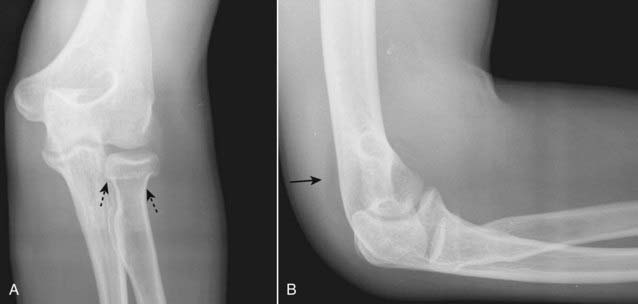

Figure 22-27 Fracture of radial head with joint effusion, frontal (A) and lateral (B) views.

Radial head fractures (dotted black arrows) are the most common fractures of the elbow in an adult. Look for fat appearing as a crescentic lucency along the dorsal aspect of the distal humerus (solid black arrow) caused by intracapsular, extrasynovial fat that is lifted away from the bone by swelling of the joint capsule due to a traumatic hemarthrosis—the positive posterior fat-pad sign. Virtually all studies of bones will include at least two views at 90° angles to each other called orthogonal views. Many protocols call for two additional oblique views which enable you to visualize more of the cortex in profile.

image

Figure 22-28 Supracondylar fracture.

A supracondylar fracture of the distal humerus is a common fracture in children, and its findings may be subtle. Most of these fractures produce posterior displacement of the capitellum of the distal humerus. On a true lateral film, the anterior humeral line (a line drawn tangential to the anterior humeral cortex and shown here in black) should bisect the middle portion of the capitellum (solid white arrow). When there is a supracondylar fracture, this line will pass more anteriorly, as it does here. There is a positive posterior fat pad sign present (solid black arrow).